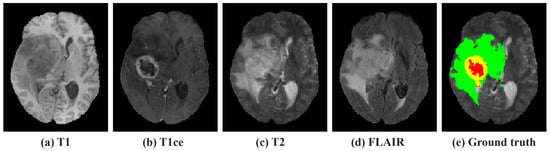

However, despite significant advancements in automatic brain tumor segmentation research, researchers have often overlooked the full potential of leveraging the unique characteristics of 3D MRI data. While 3D-based models align more closely with the intrinsic volumetric nature of MRI data, processing 3D data with convolution layers that utilize kernels fails to fully exploit the unique characteristics of MRI. MRI inherently comprises three dimensions—axial, coronal, and sagittal—each providing unique and critical perspectives on brain anatomy and pathology, as illustrated in Figure 1. Focusing on the axial, coronal, and sagittal dimensions is essential because each dimension offers a different view of the brain’s anatomy, revealing various aspects of tumors, such as their spread, volume, and interaction with surrounding tissues [22,23]. This highlights the need for a novel approach that not only preserves the rich contextual and spatial nuances inherent in MRI data but also enhances tumor segmentation precision by deeply prompting the understanding of the multi-axis structure of MRI data.

Figure 1.

Three-axis visualization of Magnetic Resonance Imaging (MRI) data. (a) Axial, (b) coronal, (c) sagittal. The colors indicate regions of tumors. Red: necrosis and non-enhancing tumor (NCR/NET); yellow: enhancing tumor (ET); green: edema (ED).